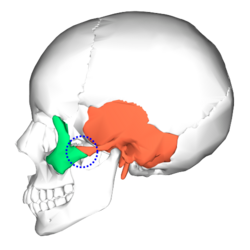

| zygomaticotemporal suture

- zygomaticomaxillary & zygomaticotemporal: Zygopushing both laterally and forwards with neck assistance. sessions will be paired with the thumbpulling ones, also lasting 1 min. I haven't found a good source that compiles everything about zygopushing so I might do a thread explaining everything with better depth but if everyone thinks it's cope I might as well gatekeep.